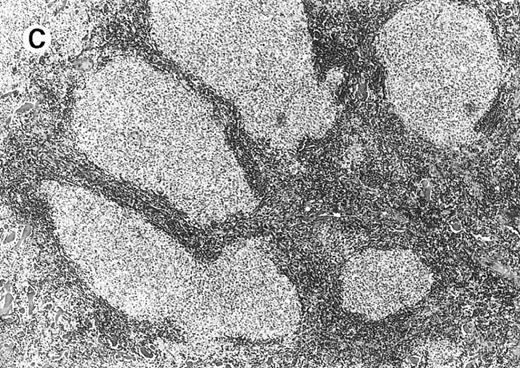

Cytomorphology.

Centroblasts and centrocytes evident within a follicle (patient 3).

All cases of follicular lymphoma were classified as grade 2 according to the REAL classification. Histology showed bottom-heavy lymphoid infiltrates with prominent follicular pattern (Figures3 and 4). A well-formed mantle zone around most follicles was present only in 2 patients. In the other specimens the mantle zone was either reduced (11 patients) or nearly absent (2 patients) (Figure5). A clear-cut marginal zone was never observed. Tingible body macrophages within follicles were present only in 1 patient and were absent in the other 14 patients. Cytomorphology of follicles in all patients showed variable proportions of centrocytes (cleaved follicle center cells) and centroblasts (Figure6). The interfollicular areas revealed the presence of small lymphocytes and histiocytes admixed with a few larger cells and occasionally other inflammatory cells such as eosinophils and plasma cells.